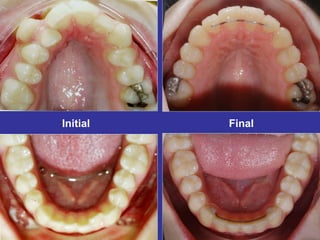

Response to Light Forces

Force Management